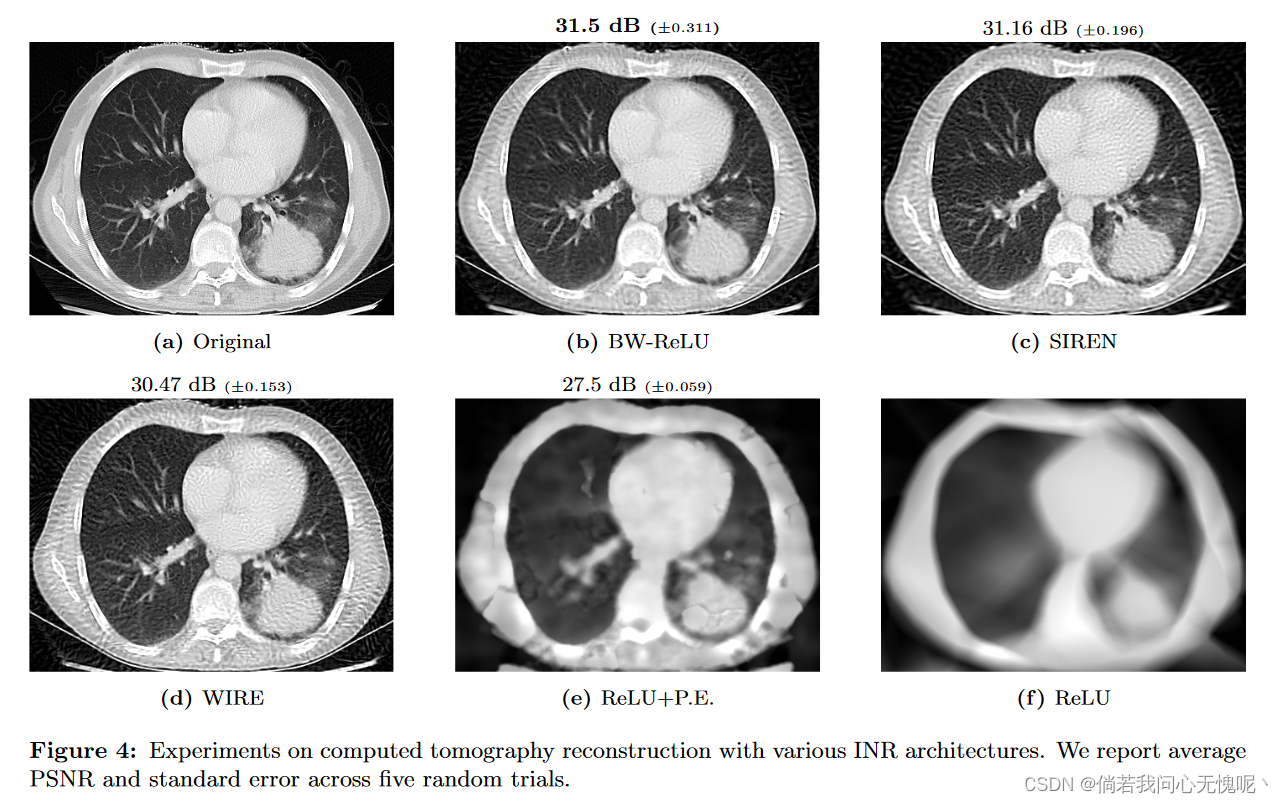

5.1 Computed Tomography(CT) Reconstruction

在本实验中,我们通过对326 × 435胸片图像进行100次等间隔CT测量来模拟CT重建(Clark et al., 2013)。图4显示了与其他INR体系结构相比的结果,表明我们的BW-ReLU神经网络的性能与传统的INR体系结构一样好,甚至可能略好。